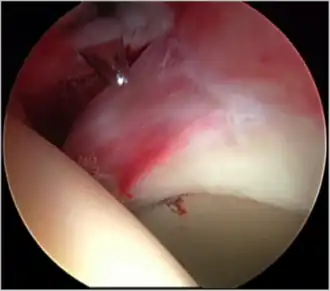

Figure 5. Portal placement under direct vision. The instrument is entering the joint through the hip capsule, between the femoral head (on the left) and acetabular labrum (on the right)